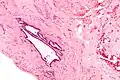

Endosalpingiosis is diagnosed by a pathologist on excision (e.g. biopsy).

It is characterized by cysts with tubal-type epithelium (e.g. ciliated epithelium) surrounded by a fibrous stroma. It is not often associated with hemorrhage.

High mag.